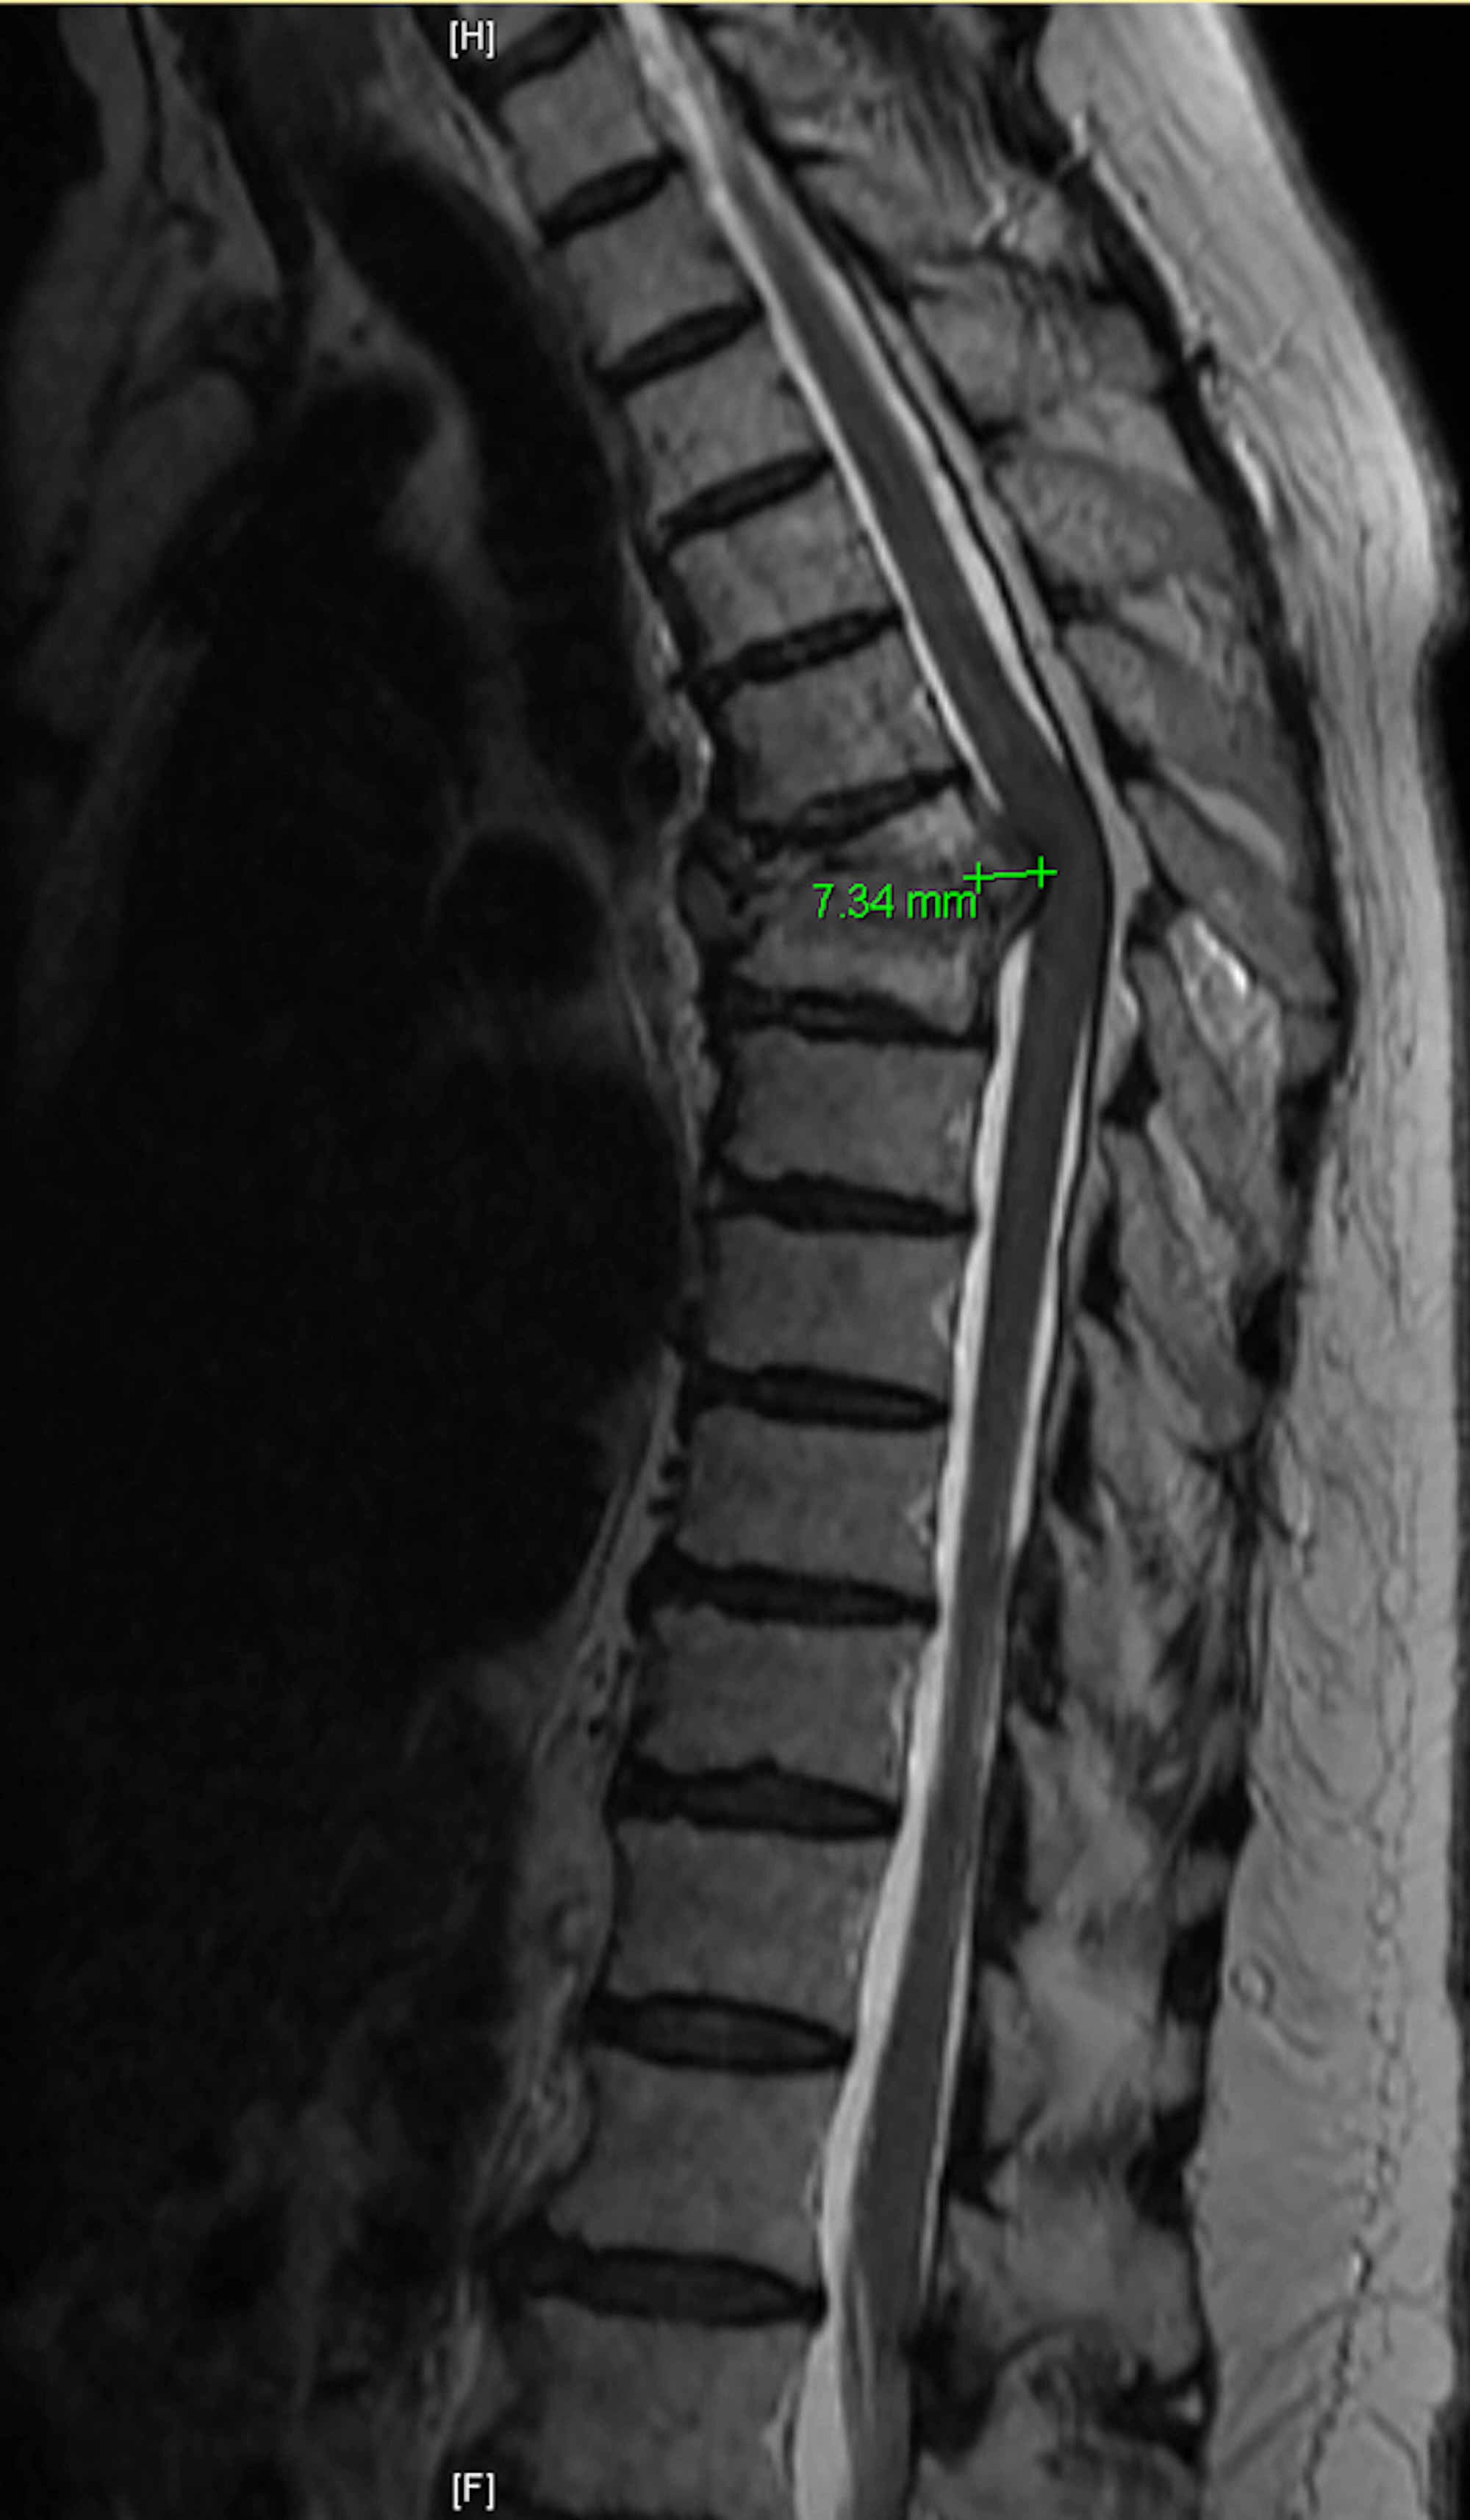

Pott's disease, MRI Stock Image M240/0490 Science Photo Library What Is Potts Disease Tuberculous spondylitis, also known as pott disease, refers to vertebral body osteomyelitis and intervertebral discitis from tuberculosis. Identify the signs and symptoms that should lead a practitioner to consider pott disease. Pott disease, also known as tuberculous spondylitis, is one of the oldest demonstrated diseases of humankind, having. Pott’s disease is a type of tuberculosis that affects your spine. The. What Is Potts Disease.

Pott's disease MRI wikidoc What Is Potts Disease Tuberculous spondylitis, also known as pott disease, refers to vertebral body osteomyelitis and intervertebral discitis from tuberculosis. Pott disease, also known as tuberculous spondylitis, is one of the oldest demonstrated diseases of humankind, having. Pott’s disease is a type of tuberculosis that affects your spine. Identify the signs and symptoms that should lead a practitioner to consider pott disease. The. What Is Potts Disease.